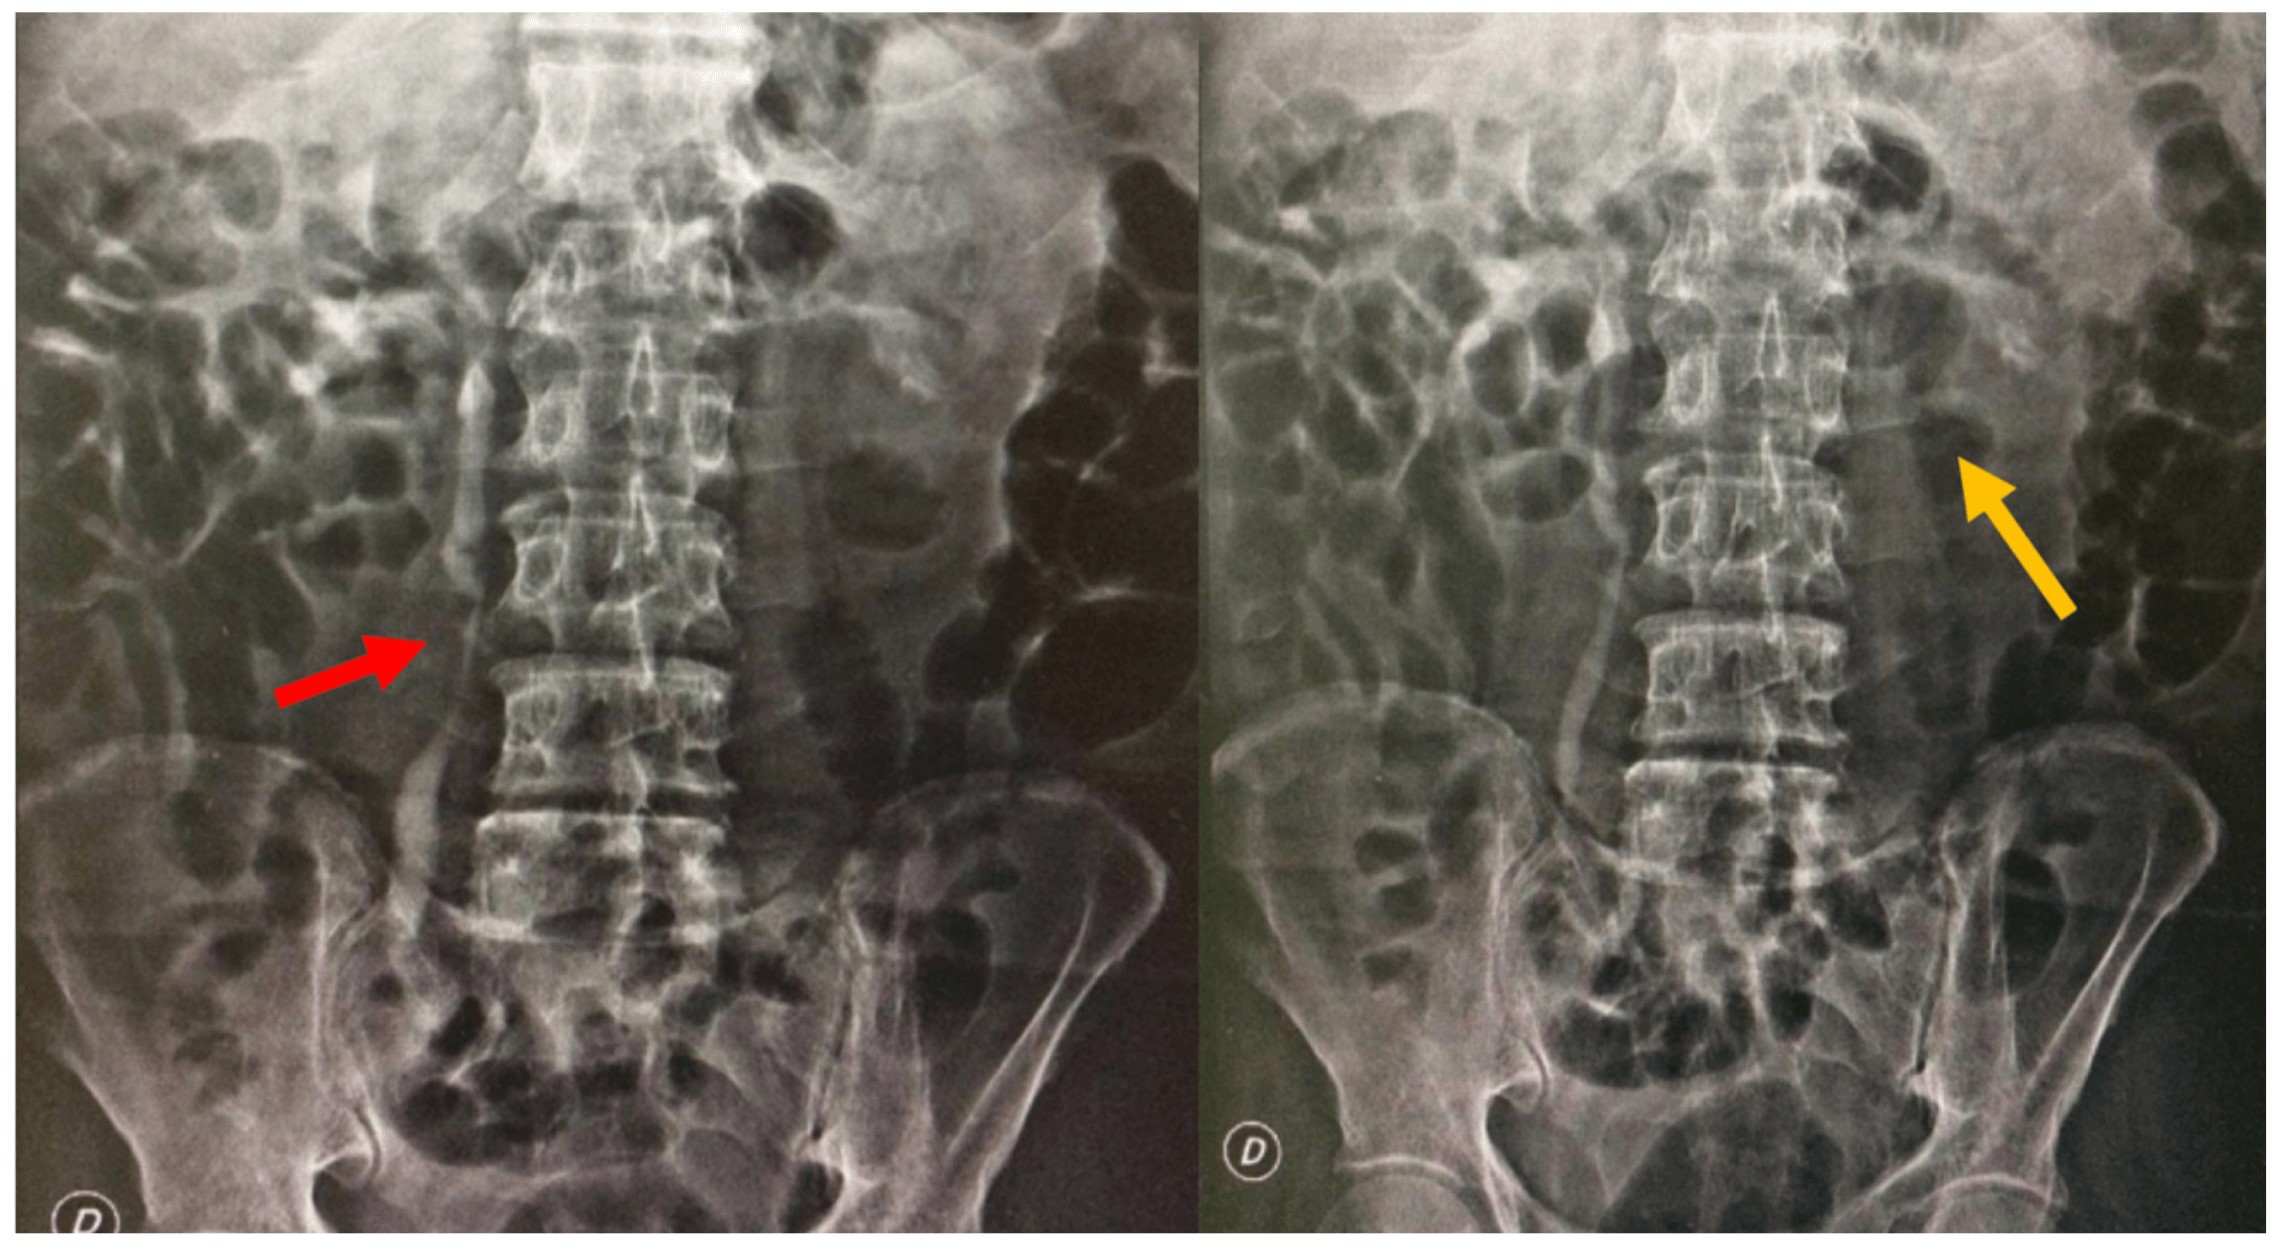

Paciente masculino de 76 años previamente asintomático y sin enfermedades de base que asiste a consulta externa de urología refiriendo aumento del contenido escrotal. Al examen físico presenta hidrocele bilateral, de predominio derecho, testículos bilaterales normotróficos sin masas, próstata de consistencia aumentada, no dolorosa. Se indica realizar hidrocelectomía y se solicita un antígeno prostático específico (PSA). Posteriormente acude a urgencias por supuración en hemiescroto derecho, asociado a fiebre, pérdida de peso y dolor testicular que no mejoró con manejo antibiótico ambulatorio. Se realiza examen físico al paciente, comprobándose su regular estado general; presenta taquicardia, deshidratación y carencia de áreas de drenaje escrotal, sin zonas crepitantes o de necrosis. Se inicia manejo antibiótico intravenoso y se solicitan paraclínicos, evidenciando leucocitosis con neutrofilia, uroanálisis con piuria estéril y elevación de azoados. La ecografía testicular no presenta hallazgos sugestivos de colecciones a nivel escrotal, por lo que se descarta el diagnóstico de absceso escrotal. Por el cuadro infeccioso a nivel escrotal se decide realizar hidrocelectomía derecha, evidenciando drenaje de aproximadamente 100 cc de líquido cetrino con epidídimo derecho engrosado caliente al tacto, el cual se punciona y drena material caseoso y purulento. Testículo derecho indurado sin áreas evidentes de secreción, por lo que se decide realizar epididimectomía derecha (Figura 1). Por hallazgos intraoperatorios de material caseoso y purulento, testículo indurado y sin foco infeccioso aparente, se sospecha tuberculosis genital, se solicitan estudios de patología y baciloscopia seriada para identificar bacilos ácido- alcohol resistente (BAAR). Se da egreso médico por adecuada evolución posoperatoria y control prioritario. El paciente consulta a urgencias a los 5 días posoperatorios con dificultad respiratoria y fiebre. Se encuentra al paciente en mal estado general, taquipneico y desaturado (saturación de oxígeno al ambiente: 85 %), requiriendo soporte ventilatorio con Venturi. La radiografía de tórax evidencia opacidades micronodulares en todo el parénquima pulmonar. Los reportes de patología y baciloscopia (BK) de epidídimo son positivos para infección por BAAR en tejido por Mycobacterium tuberculosis. Se inicia manejo tetraconjugado (Pirazinamida 1600 mg/día vía oral + Etambutol 1100 mg/día vía oral + Isoniacida 300 mg/día vía oral + Rifampicina 600 mg/día vía oral) asociado a Piridoxina 50 mg /día vía oral, por tuberculosis miliar, pulmonar y genitourinaria. Se decide solicitar ecografía de vías urinarias por la sospecha de TBCGU, evidenciando hallazgos sugestivos de dilatación pielocalicial bilateral, por lo que se solicita urografía excretora para descartar compromiso ureteral. Se evidencia retardo en la eliminación del medio de contraste bilateral asociado a dilatación ureteral bilateral de predominio derecho (Figura 2). Con estos hallazgos sugestivos de TBCGU, se realiza pielografía retrógrada bilateral (Figura 3), y por sus hallazgos se decide derivar al paciente con catéter JJ bilateral por compromiso ureteral de TBC con el fin de aliviar la dilatación pielocalicial previamente referida y evitar la progresión a falla renal. El paciente es dado de alta por infectología y urología. En el momento se encuentra asintomático con adecuados niveles de azoados.

Es de vital importancia descartar tumores testiculares e identificar que generalmente la infección por tuberculosis empieza en el epidídimo, y que se extiende al testículo de forma tardía. La epididimitis tuberculosa se presenta como un epidídimo alargado con lesiones nodulares heterogéneas e hipoecoicas. Las imágenes radiológicas no serán útiles en estadios tempranos (3,9,18). Hallazgos ecográficos de orquitis incluyen testículos hipoecoicos homogéneos o heterogéneos, o testículos alargados nodulares heterogéneos e hipoecoicos. Otros hallazgos incluyen engrosamiento de la piel escrotal, hidrocele, abscesos escrotales y fístulas (9). Por lo tanto, una lesión testicular asociada a compromiso del epidídimo y engrosamiento de la piel favorece el diagnóstico de TBCGU (6). La pielografía intravenosa está indicada en pacientes con leucocituria y anormalidades en estudios ecográficos, como en el paciente documentado, que tenía dilatación pielocalicial. La urografía excretora puede detectar signos como distorsión de los cálices, calcificaciones, estenosis de uréter y fibrosis vesical (19), como los evidenciados en este caso.